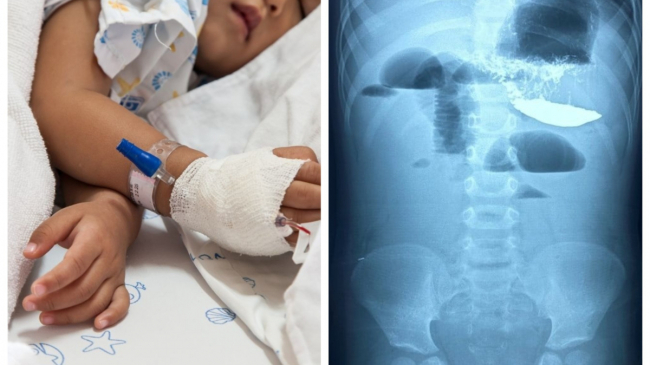

Un copil în vârstă de doar doi anișori a ajuns în stare gravă la Unitatea Primiri Urgențe a Institutului Mamei și Copilului din capitală, în data de 1 octombrie 2021, cu acuze la vome multiple, deshidratare, apatie, slăbiciune generală și fatigabilitate. Mama copilului spune că micuțul a început a vomita în data de 30 septembrie. Cu părere de rău, reprizele de vomă devenise tot mai frecvente, ajungând până la 15.

După efectuarea mai multor investigații inclusiv Radiografia de ansamblu a abdomenului, medicii au stabilit diagnoza de Boală aderențială avansată, Ocluzie intestinală joasă.

Pacientul a fost internat în mod urgent în secția Reanimare Chirurgicală, unde după o pregătire preoperatorie s-a intervenit chirurgical. La revizie s-a constatat multiple aderențe şi bride care provocau multiple angulații. Intraoperator s-a constatat malrotație intestinală cu mezou comun cu întreg colonul plasat pe stânga inclusiv unghiul iliocecal cu apendicele viermiform.

De asemenea a fost constatat un defect aderențial major în regiunea plastiei defectului diafragmatic congenital cu implicarea omentului anselor intestinale si colonului. S-a recurs la procedeul de adezioliză cu înlăturarea zonelor de angulații şi restabilirea permeabilității lumenului intestinal. După reîntoarcerea anselor în cavitatea abdominală s-a constatat o ameliorare parțială a fenomenelor circulatorii a lumenului intestinal.

Postoperator pacientul se află sub supravegherea medicilor, iar după perioada de reabilitare urmează a fi externat la domiciliu. Potrivit medicilor, copilul este dezvoltat fizic și psihic conform vârstei și a fost diagnosticat anterior cu Hernie diafragmatică.